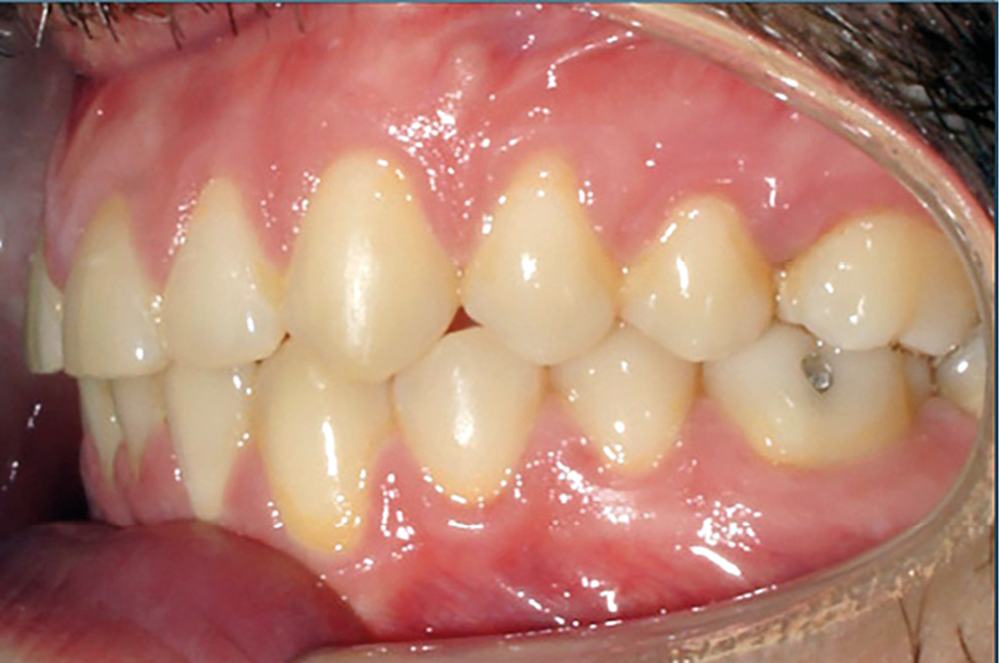

Examen endobuccal (fig. 2a-e)

L’arcade maxillaire est asymétrique, en hémi-lyre droite. Elle présente une mésio-position du secteur 1 en lien avec un encombrement antérieur estimé à 4 mm, se traduisant par une palato-position de la 12 et une rotation de la 11. On observe également des mésio-rotations des premières molaires et une palato-version incisive. L’arcade mandibulaire est ellipsoïde et présente un léger encombrement incisif (1 mm).

Concernant les relations occlusales, on observe une classe II complète subdivision droite. Le surplomb est absent et le recouvrement augmenté, estimé à 4 mm, a provoqué une usure des bords libres de 11 et 21 par attrition. Dans la dimension transversale, on constate une endoalvéolie maxillaire, ainsi qu’une concordance des médianes incisives entre elles, mais toutes deux déviées à droite par rapport au plan sagittal médian.